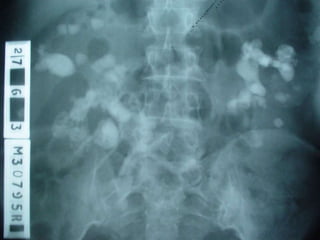

Investigations

i.v.u

19

20

21

22